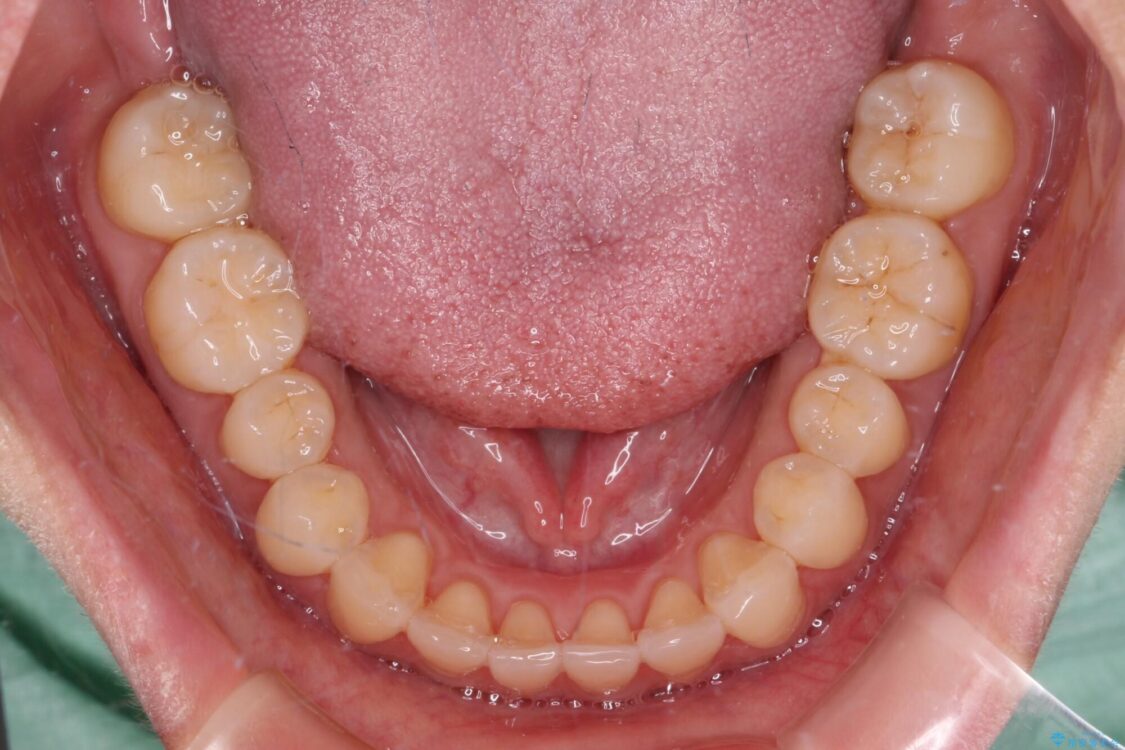

治療前

• 【モニター】前歯のデコボコをインビザラインで改善 治療前画像